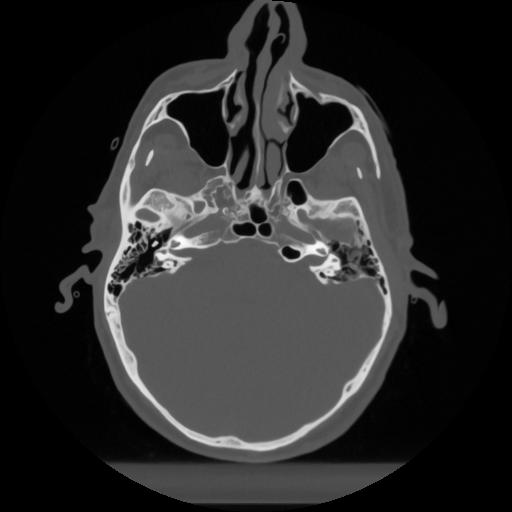

12 P.BLANDAS,,Vol,0.5,P.BLANDAS,,